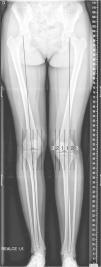

La medición radiológica fue realizada sobre telemetrías de miembros inferiores. La medición de la asimetría inicial (última radiografía previa a la cirugía) y residual (postepifisiodesis en el momento de la madurez esquelética) fue realizada por un único observador entrenado con un error técnico de medición (ETM) de 1,1 mm. En la figura 1 se muestran las reparos radiológicos para la medición de miembros inferiores, siguiendo los criterios descritos por Sánchez16.

Otro observador entrenado (JC) registró las complicaciones posquirúrgicas. Estas se dividieron en perioperatorias inmediatas y alejadas. Se definió sobre corrección cuando se invirtió la asimetría en la adultez en más de 1 cm18. Para la evaluación de la deformidad angular del miembro operado se utilizaron las zonas o cuadrantes del eje mecánico, como muestra la figura 2.19 Se consideró alteración del eje mecánico como complicación posquirúrgica si la desviación de este no estaba presente en la radiografía inicial o esta había aumentado más de 1 cuadrante o había cambiado de zona.